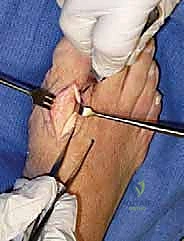

1. استئصال النتوءات العظمية (Cheilectomy)

- لمن تصلح؟ المراحل المبكرة والمتوسطة (1 و 2) حيث لا يزال هناك غضروف جيد في المفصل.

- ما هي؟ جراحة يتم فيها "تنظيف" المفصل. يقوم الجراح بإزالة النتوءات العظمية (Bone Spurs) من أعلى المفصل، بالإضافة إلى إزالة جزء صغير من أعلى رأس عظمة المشط.

- الهدف: إزالة العائق الميكانيكي الذي يمنع حركة الإبهام لأعلى، مما يخفف الألم ويحسن نطاق الحركة.